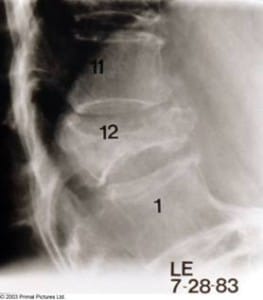

COMPRESSION FRACTURES

Compression fractures are common fractures found in both the thoracic and lumbar spine and result from trauma involving a combination of compression and flexion. In the elderly, osteoporosis is a frequent contributing factor to the development of these wedge-shaped fractures – and these so called “grandma fractures” can also occur spontaneously during everyday activities such as coughing or sneezing.

Osteoporosis may result in vertebral compression, which can be acutely painful or pass unnoticed by the patient. Wedging usually affects the upper end-plate more than the lower, so that the difference in height between the front and back of the normally rectangular shaped vertebrae is greater than 2mm.